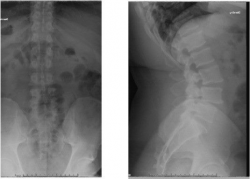

發稿日期:114年1月2日 臺北市立聯合醫院中興院區骨科主治醫師劉彥麟曾經遇過一位眉頭深鎖的病患,一跛一跛的走進診間,苦惱的說:「醫生,我沒辦法好好走路已經有一段時間了,雙腳站一下就很痠痛麻木不舒服,諮詢過很多醫院都建議開刀,不知道你的意見如何?」從當時病患的X光影像可以看出來,第三腰椎至第五腰椎滑脫,且外院的核磁共振影像也顯示有嚴重的椎管狹窄,病人表示已接受過藥物保守治療以及復健...... [閱讀更多]